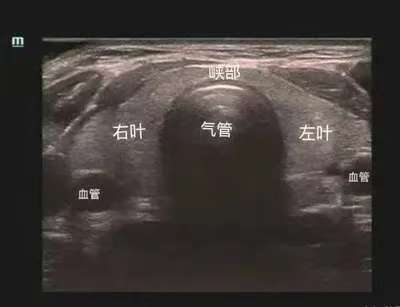

什么是甲狀腺超聲檢查?

甲狀腺超聲檢查是一種無(wú)創(chuàng)、便捷、檢出率高、可重復(fù)的檢查方法,檢查過(guò)程能夠清晰地顯示甲狀腺的大小、形態(tài)、結(jié)構(gòu)以及血流情況。通過(guò)超聲檢查,我們可以及早地發(fā)現(xiàn)甲狀腺結(jié)節(jié)、甲狀腺炎、甲狀腺腫瘤等疾病,這些疾病在早期可能沒有明顯的癥狀,但超聲檢查能夠準(zhǔn)確地發(fā)現(xiàn)它們的存在,為后續(xù)的診斷和治療提供重要依據(jù)。此外,超聲檢查還可以對(duì)甲狀腺結(jié)節(jié)進(jìn)行良惡性鑒別,幫助醫(yī)生制定最合適的治療方案,為及時(shí)治療提供有力依據(jù)。